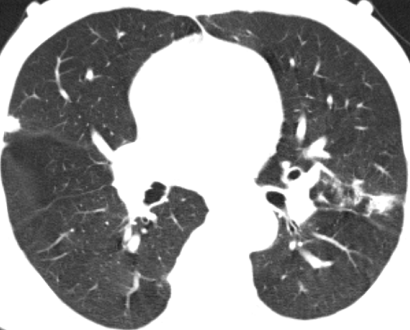

入住肺病科(呼吸内科)后,医生为患者完善了胸部CT及相关检查。影像结果显示:“双肺见片状密度增高影及实变影,边界模糊,提示双肺感染。”针对患者病情,科室立即组织了病例讨论。专家们凭借着深厚的医学知识和丰富的临床经验,深入分析病情,制定出了科学合理的诊疗方案,一天内完成了相关检查。

治疗前CT影像▲